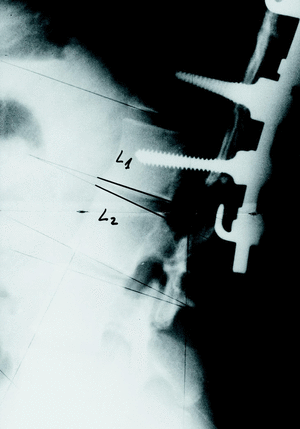

En 2 pacientes se soltó el material inferior, acompañándose de cifosis del DFI en uno de ellos (fig. 3), en el que no se incluyó en la instrumentación el primer disco en lordosis; hay que destacar que no hubo aflojamiento del material cuando se emplearon tornillos pediculares como anclaje caudal.

Figura 3. Suelta de uñas en el extremo inferior de la instrumentación y cifosis del DFI.

Dada la dificultad de medir, en muchas ocasiones, la cifosis del Disco Frontera Superior, asumimos que tiene lugar cuando se suelta el material proximalmente (fig. 4), que ocurrió en 4 casos.

Figura 4. Suelta de uñas en el extremo superior de la instrumentación.